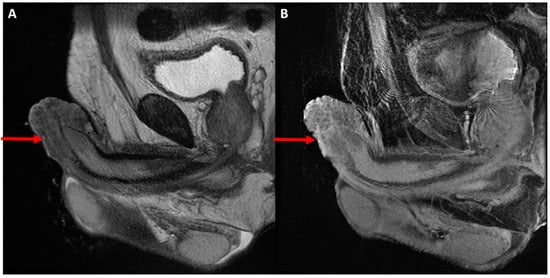

4. Magnetic Resonance Imaging

4.1. Primary Staging

4.2. Restaging and Post-Treatment Surveillance